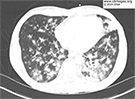

A middle-aged man with HIV infection developed fever, a productive cough and pleuritic chest pain. » |